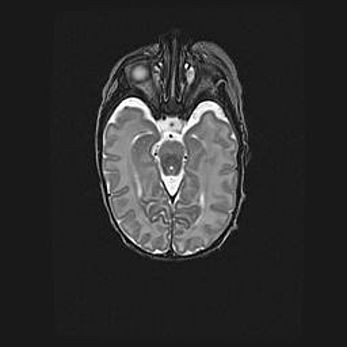

Множественные кисты обоих полушарий головного мозга, наибольшая из них в правой затылочной области. Ассиметричная атрофическая гидроцефалия.

Возраст: 7 месяцев

Вес: 5660 г

Пол: мужской

Окружность головы: 41,5 см

Срок гестации: 28-29 недель

Кисты головного мозга развиваются в результате многоочаговых некрозов вещества мозга и возникают вследствие перенесенной перинатальной инфекции, менингитов, энцефалитов, асфиксии, родовой травмы, расстройств мозгового кровообращения различного генеза. Образованию кист в веществе головного мозга плодов и новорожденных способствуют такие факторы, как высокое содержание в нем воды, недостаточная (или отсутствие) миелинизация и слабая астроглиальная реакция на повреждение.

Кисты могут сочетаться с гидроцефалией и другими поражениями головного мозга.